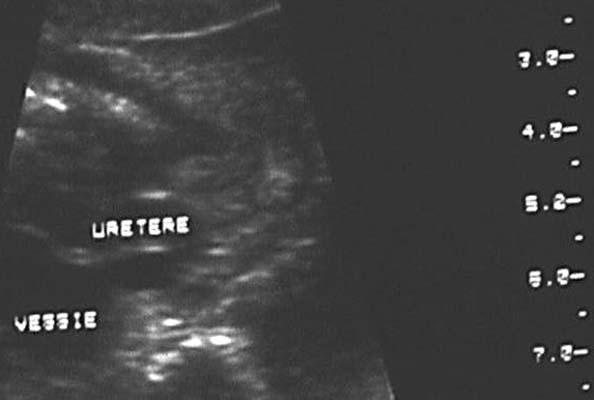

Dilatation urétérale : Structure tubulée à contenu anéchogène, rectiligne ou tortueuse, pouvant présenter des variations de calibre en rapport avec le péristaltisme.

- Reflux vésico-urétéral (La variabilité avec le temps et la visualisation de l’uretère ou la majoration de la dilatation au cours d’une miction sont en faveur d’un reflux)

Si urétéro-hydronéphrose bilatérale, rechercher une vessie anormale évocatrice d’un obstacle urétro-vésical.